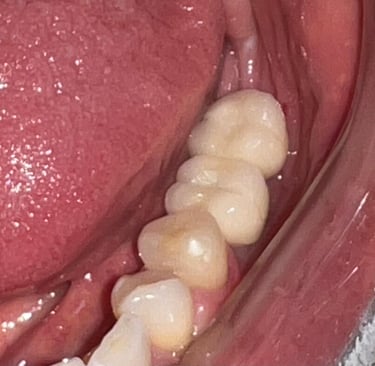

Aspecto clínico final - Imagens originais — nenhuma contém retoques

Caso da cirurgia guiada dispensando o enxerto - Imagens originais — nenhuma contém retoques

Aspecto Clínico Final - Fotografias originais — nenhuma contém retoques — A cor dos dentes é escolhida de acordo com o gosto e a preferência estética de cada paciente.